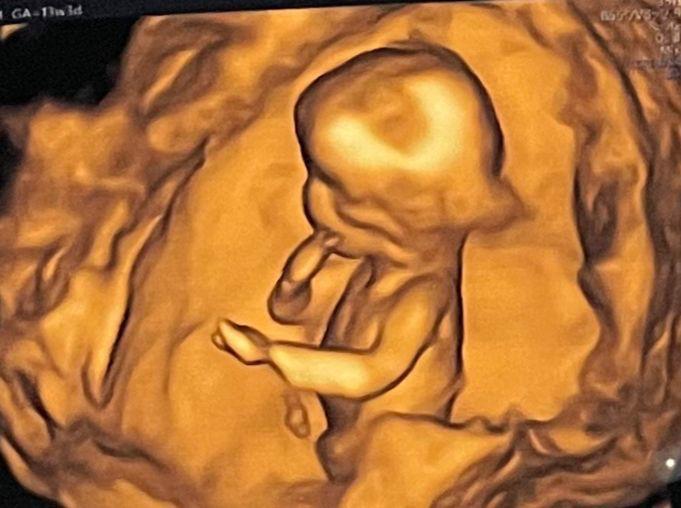

In mid-October our gynaec sent us for our NT scan. It’s a test where the nuchal fluid behind the baby’s neck is measured. A high level indicates that there’s a 80% chance of your baby having genetic defects like Down syndrome. Our hearts broke when we saw our reading. It was 3.92, whereas the normal is not more than 2.5. We were so upset. And when our gynaec said this is the highest she’s ever seen, I was a mess. We cried bitterly when we returned. That period is probably the most I’ve fought with God. Why all this when we do so much for you and the church? Why!?

I wasn’t happy with the test, so Dr. Payal sent us to one of the best fetal specialists in Pune, Dr. Pooja Lodha. Our appointment was at 1pm but we finally went in at around 4pm. The NT this time was 2.6, still high. But again, Dr. Pooja took her time to explain everything to us in great detail. We had two issues, one where the pressure at the artery supplying blood to baby was high. And secondly there were multiple fibroids. She said it’ll be a miracle if we have a normal delivery.

Dr. Pooja is definitely a gem of a person and absolutely fantastic at what she does. Again we were blessed with the best. What we loved the most are the lovely pics she shared of baby at almost every visit of ours.